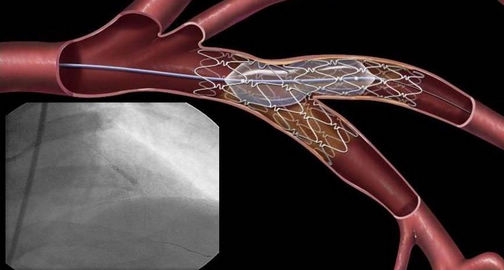

激光切割技術(shù)在心血管支架加工方法上另辟蹊徑

激光切割技術(shù)在心血管支架上的應(yīng)用一種革命性切割技術(shù),是一種全新的精密切割加工工藝,正是心血管支架屬于一類精密結(jié)構(gòu),在球囊血管成形術(shù)治療阻塞的靜脈或動(dòng)脈之后需要將其植入人體血管中,達(dá)到物理擴(kuò)張血管的作用,因而,為確保植入產(chǎn)品為綠色無污染的器件,可以達(dá)到支撐的強(qiáng)度,同時(shí),支架表面還不能有任何行毛剌等都必需使用激光切割才能突破傳統(tǒng)焊接對各項(xiàng)工藝的條件限制,專業(yè)心血管支架激光切割機(jī)發(fā)揮得不可替代的作用。

一臺(tái)好的心血管支架激光切割機(jī)離不開功率穩(wěn)定的激光器與運(yùn)動(dòng)控制系統(tǒng),這與其切割質(zhì)量工藝關(guān)系非常密切,所以處于醫(yī)療器械生產(chǎn)制造業(yè),激光切割機(jī)設(shè)備需要一套高質(zhì)量,高可靠的設(shè)備,這樣才能高精度,高速度完成對支架的切割,通過電腦控制軟件,能實(shí)時(shí)反饋各項(xiàng)加工參數(shù),及時(shí)了解加工狀態(tài),另一個(gè)優(yōu)點(diǎn)就是激光切割非接觸加工,無外部機(jī)械壓力,不會(huì)造成支架外部受損,配合高精密的視覺定位系統(tǒng),操作簡單,切割精確度高。

光纖激光切割機(jī)具有光束質(zhì)量好,光斑大小統(tǒng)一性強(qiáng),能量穩(wěn)定,特別適合于需要表面光滑,邊緣 不得有毛剌的切割工藝要求的加工,而心血管支架就需要這樣的加工藝水平,因而在眾多的激光切割機(jī)類型中,光纖激光切割最適合應(yīng)用于此類加工。另外,激光技術(shù)的發(fā)展也促進(jìn)了其相關(guān)技術(shù)的廣泛應(yīng)用,比如激光焊接,激光打標(biāo),而必血管支架 為了理好的管理,追蹤,也需要采用激光打標(biāo)相關(guān)的型號(hào),日期,材料信息等內(nèi)容,具有標(biāo)刻美觀 ,永不消失物特點(diǎn),又條例無污染虧輻射的需要求,因此,激光技術(shù)未來將在醫(yī)療器件得了更好的 發(fā)揮作用。